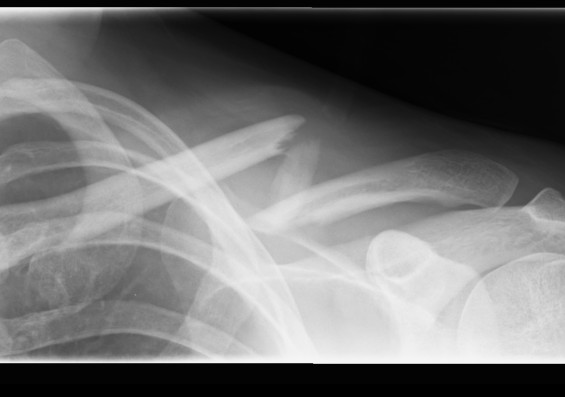

Q4

Where is the fracture here?

A comminuted fracture of the clavicle (collar bone)